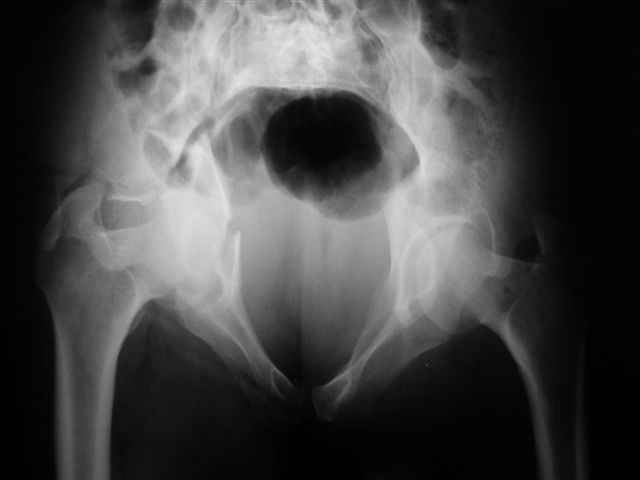

Спасибо за комментарии и рекомендации. Откровенно говоря, больного я прооперировал на прошлой неделе, через 5 дней после аварии и проблем с ним пока никаких нет, на удивление при достаточно обширной диссекции (илиофеморальный доступ) болей практически нет, так что больной самостоятельно садится в кровати, выполняет активные движения в оперированном суставе, сгибая до 60 градусов пока, далее с ассистенцией.

Причиной обращения к сообществу были возникшие непосредственно после операции сомнения и разочарования полученным качеством репозиции: а надо ли было трогать перелом вообще, репозиция передней колонны технически была очень сложна для меня, хотя реконструкции была в той же последовательности, что Д-р А.В.Рунков рекомендовал, в какой-то момент безуспешных манипуляций стал думать о *вторичной конгруэнтности*, которую не так давно обсуждали на

форуме и скелетном вытяжении. С репозицией и фиксацией задней колонны и отдельно задне-верхней стенки впадины проблем не возникло. Послеоп. Рг граммы в приложении. Если возникнут какие-либо дополнения или поправки - был бы признателен.